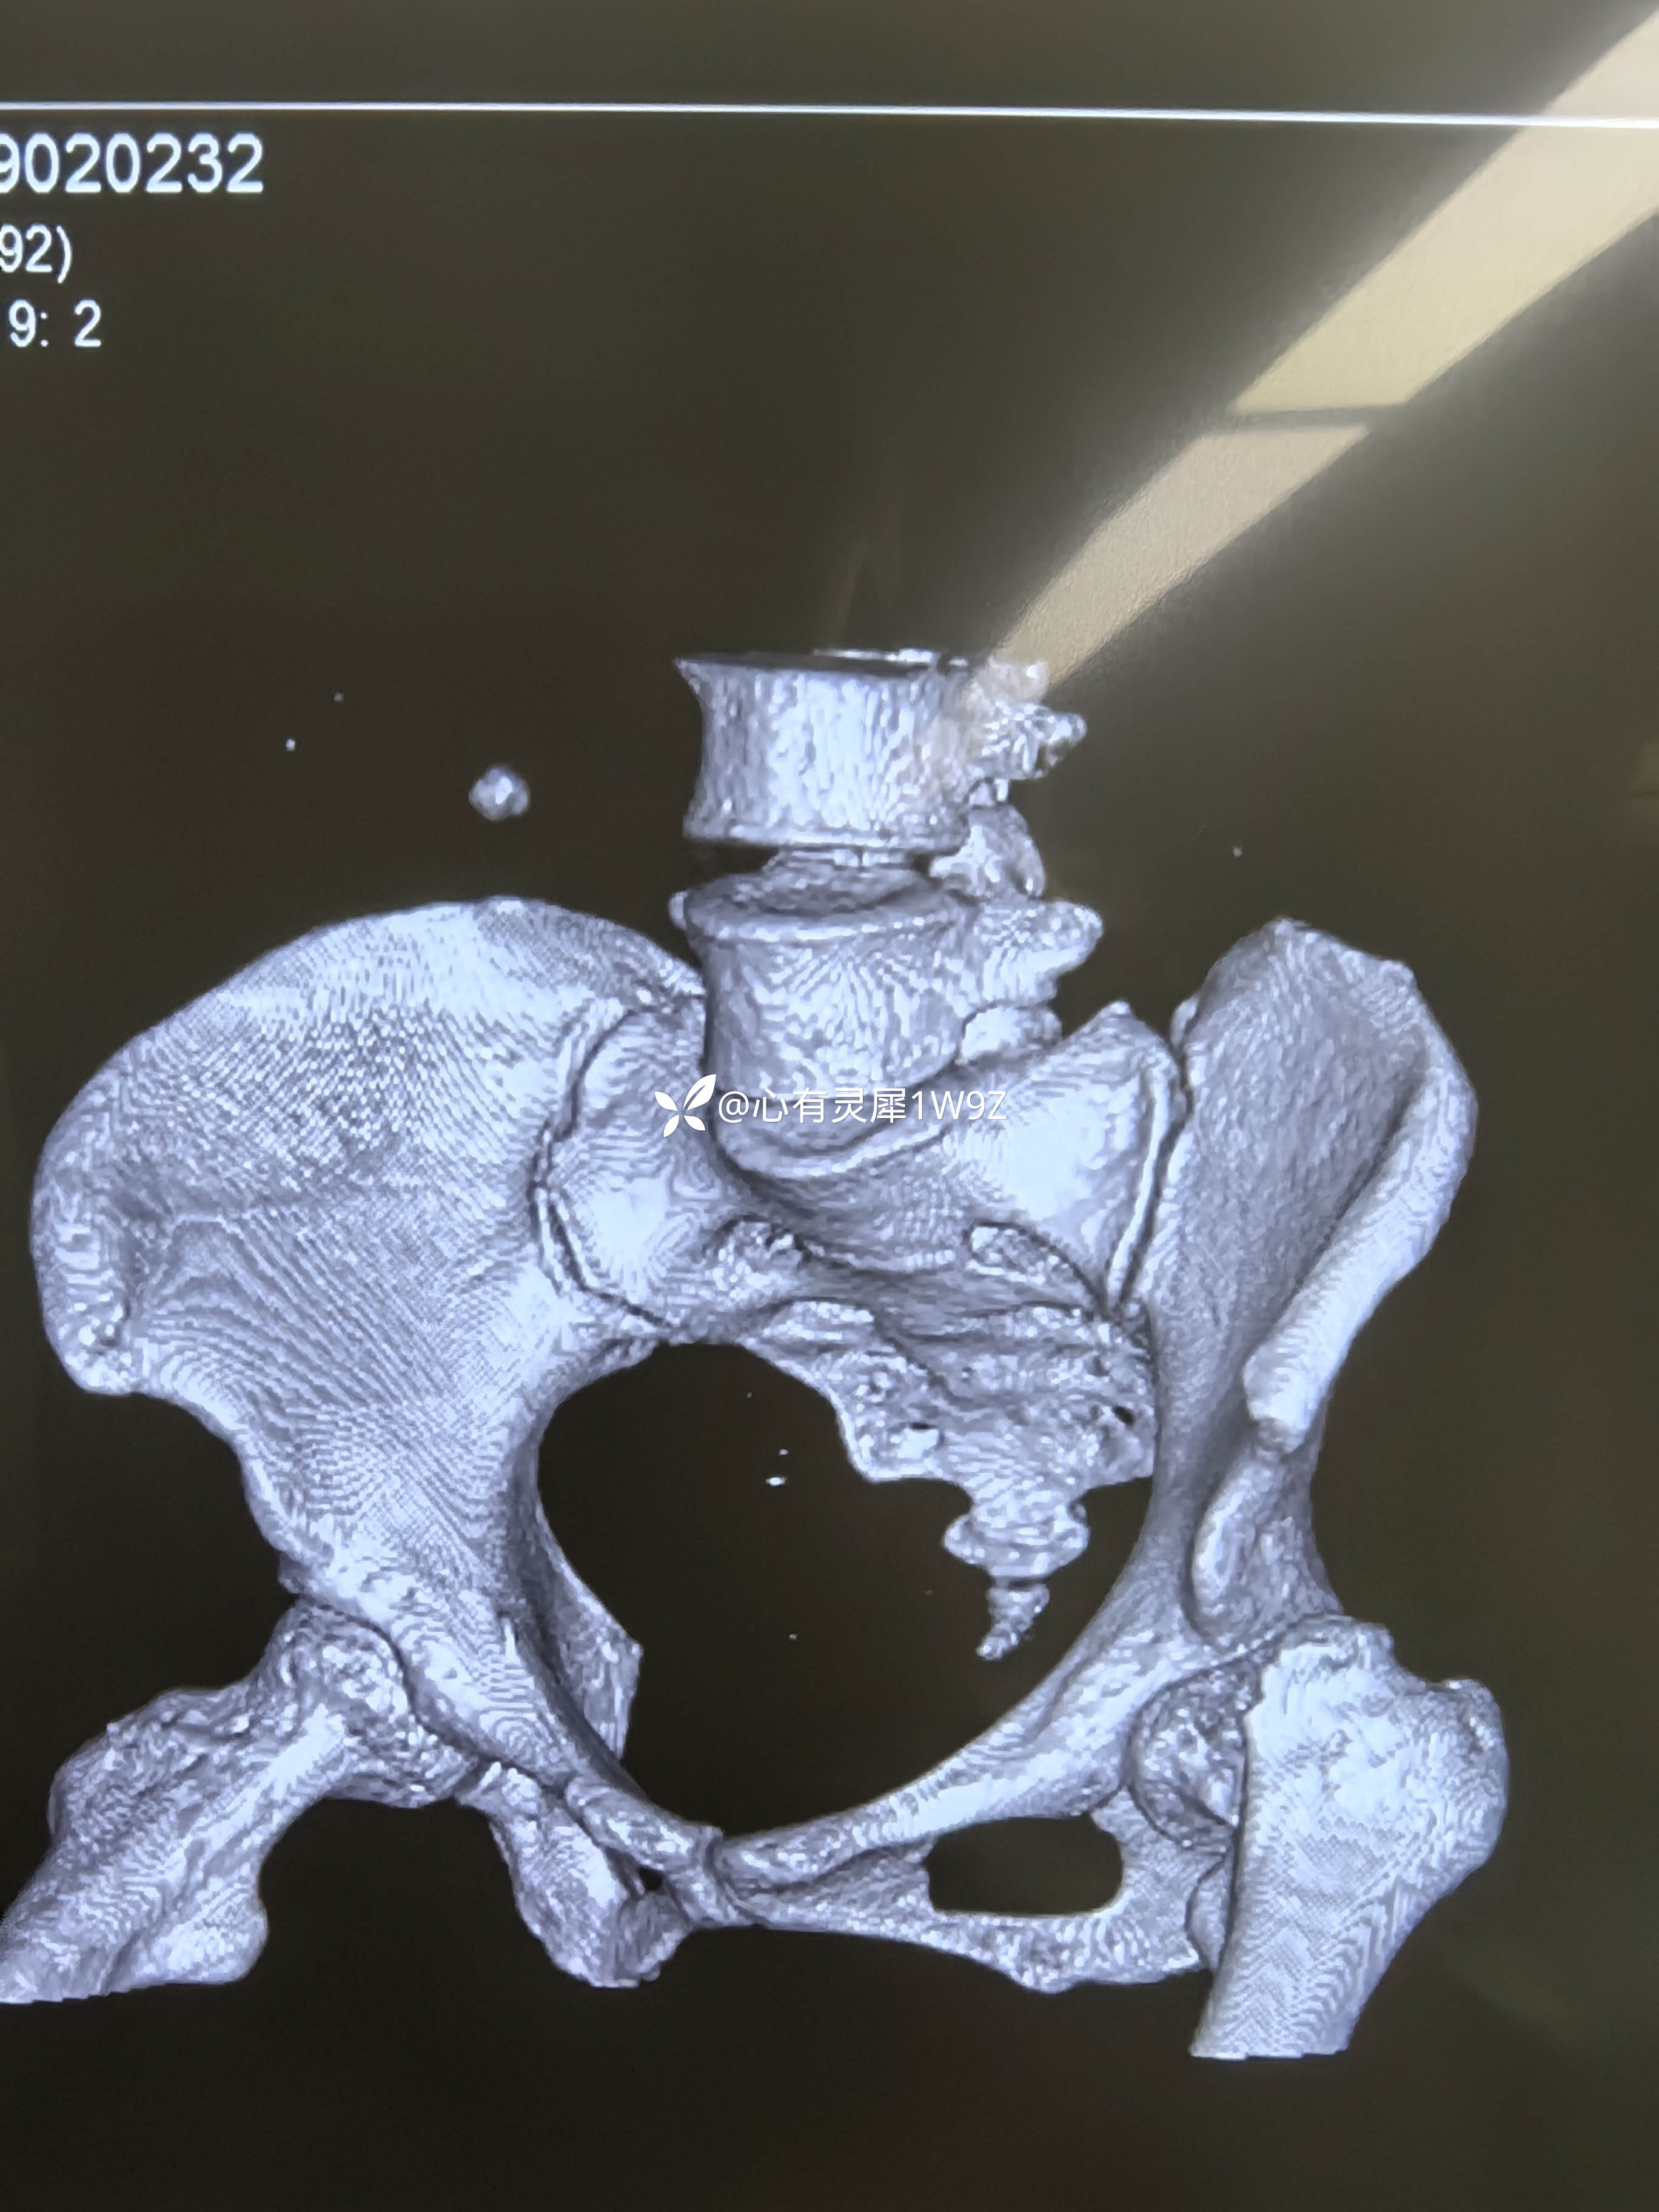

诊断:左侧股骨颈骨折(头下型)garden IV型

向患者及家属讲解治疗方案。患者和家属选择做内固定。积极准备后在24小时内手术。椎管麻醉,手术顺利,计划首先闭合复位,复位失败就切开复位,三枚加压空心钉固定。

2,关于贴壁,平行,长度,角度。自己感觉这次平行和长度都比较满意,贴壁还可以,角度不是很完美,感觉可以接受,就没有再调整。